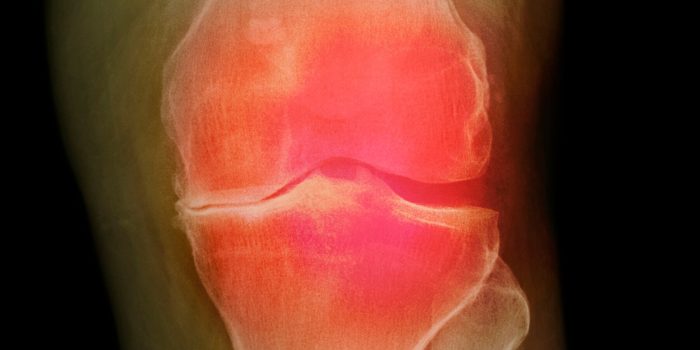

With funding from ARPA-H, three teams of researchers have regrown bone and cartilage, even entire knees, in animal studies. Human trials are not far off.